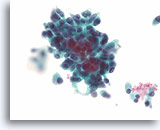

Afbeelding 19

Cellaesie, folliculair neoplasma (lymfocytische thyroïditis vs hurthlecelneoplasma) kan niet worden uitgesloten, schildklier FNA, ThinPrep®.

De hurthlecellen hebben een microfolliculaire organisatie. Er zijn een paar lymfocyten door het epitheel gemengd, hetgeen pleit voor lymfocytische thyroïditis.

60X

Afbeelding 19

Cellaesie, folliculair neoplasma (lymfocytische thyroïditis vs hurthlecelneoplasma) kan niet worden uitgesloten, schildklier FNA, ThinPrep®.

De hurthlecellen hebben een microfolliculaire organisatie. Er zijn een paar lymfocyten door het epitheel gemengd, hetgeen pleit voor lymfocytische thyroïditis.

60X